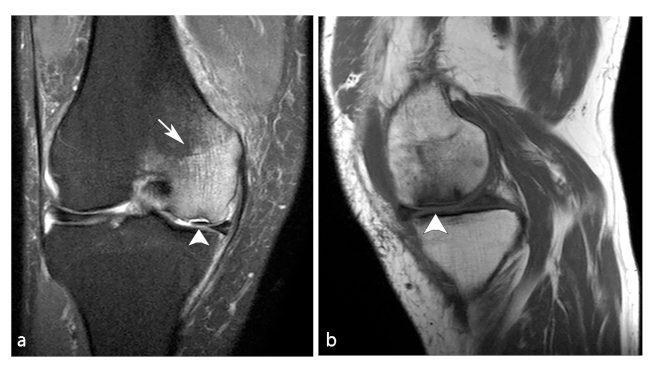

Los primeros estadios de la lesión se caracterizan por una fractura subcondral sin asociación de hallazgos osteonecróticos, reconocida en RM por una imagen lineal de baja señal ponderada en T1, subcortical, y edema periférico extenso mejor evidenciado en secuencias ponderadas en T2. Al avanzar su estadio, estas lesiones osteonecróticas muestran cambios distales por una cicatrización deficiente, lo que genera reacción y formación de cartílago con tejido fibroso indicativo de retraso o falta de unión.11

En RM en secuencia ponderada en T1, la intensidad de señal de la grasa de la médula ósea del cóndilo femoral afectado es reemplazada por un área con baja señal, asociada a una periferia de aún más baja señal (►Figs. 4 y 5).8 En la secuencia ponderada en T2 se visualiza lesión central hipointensa con área de señal alta periférica en relación al patrón de edema de la médula ósea (►Fig. 6).11